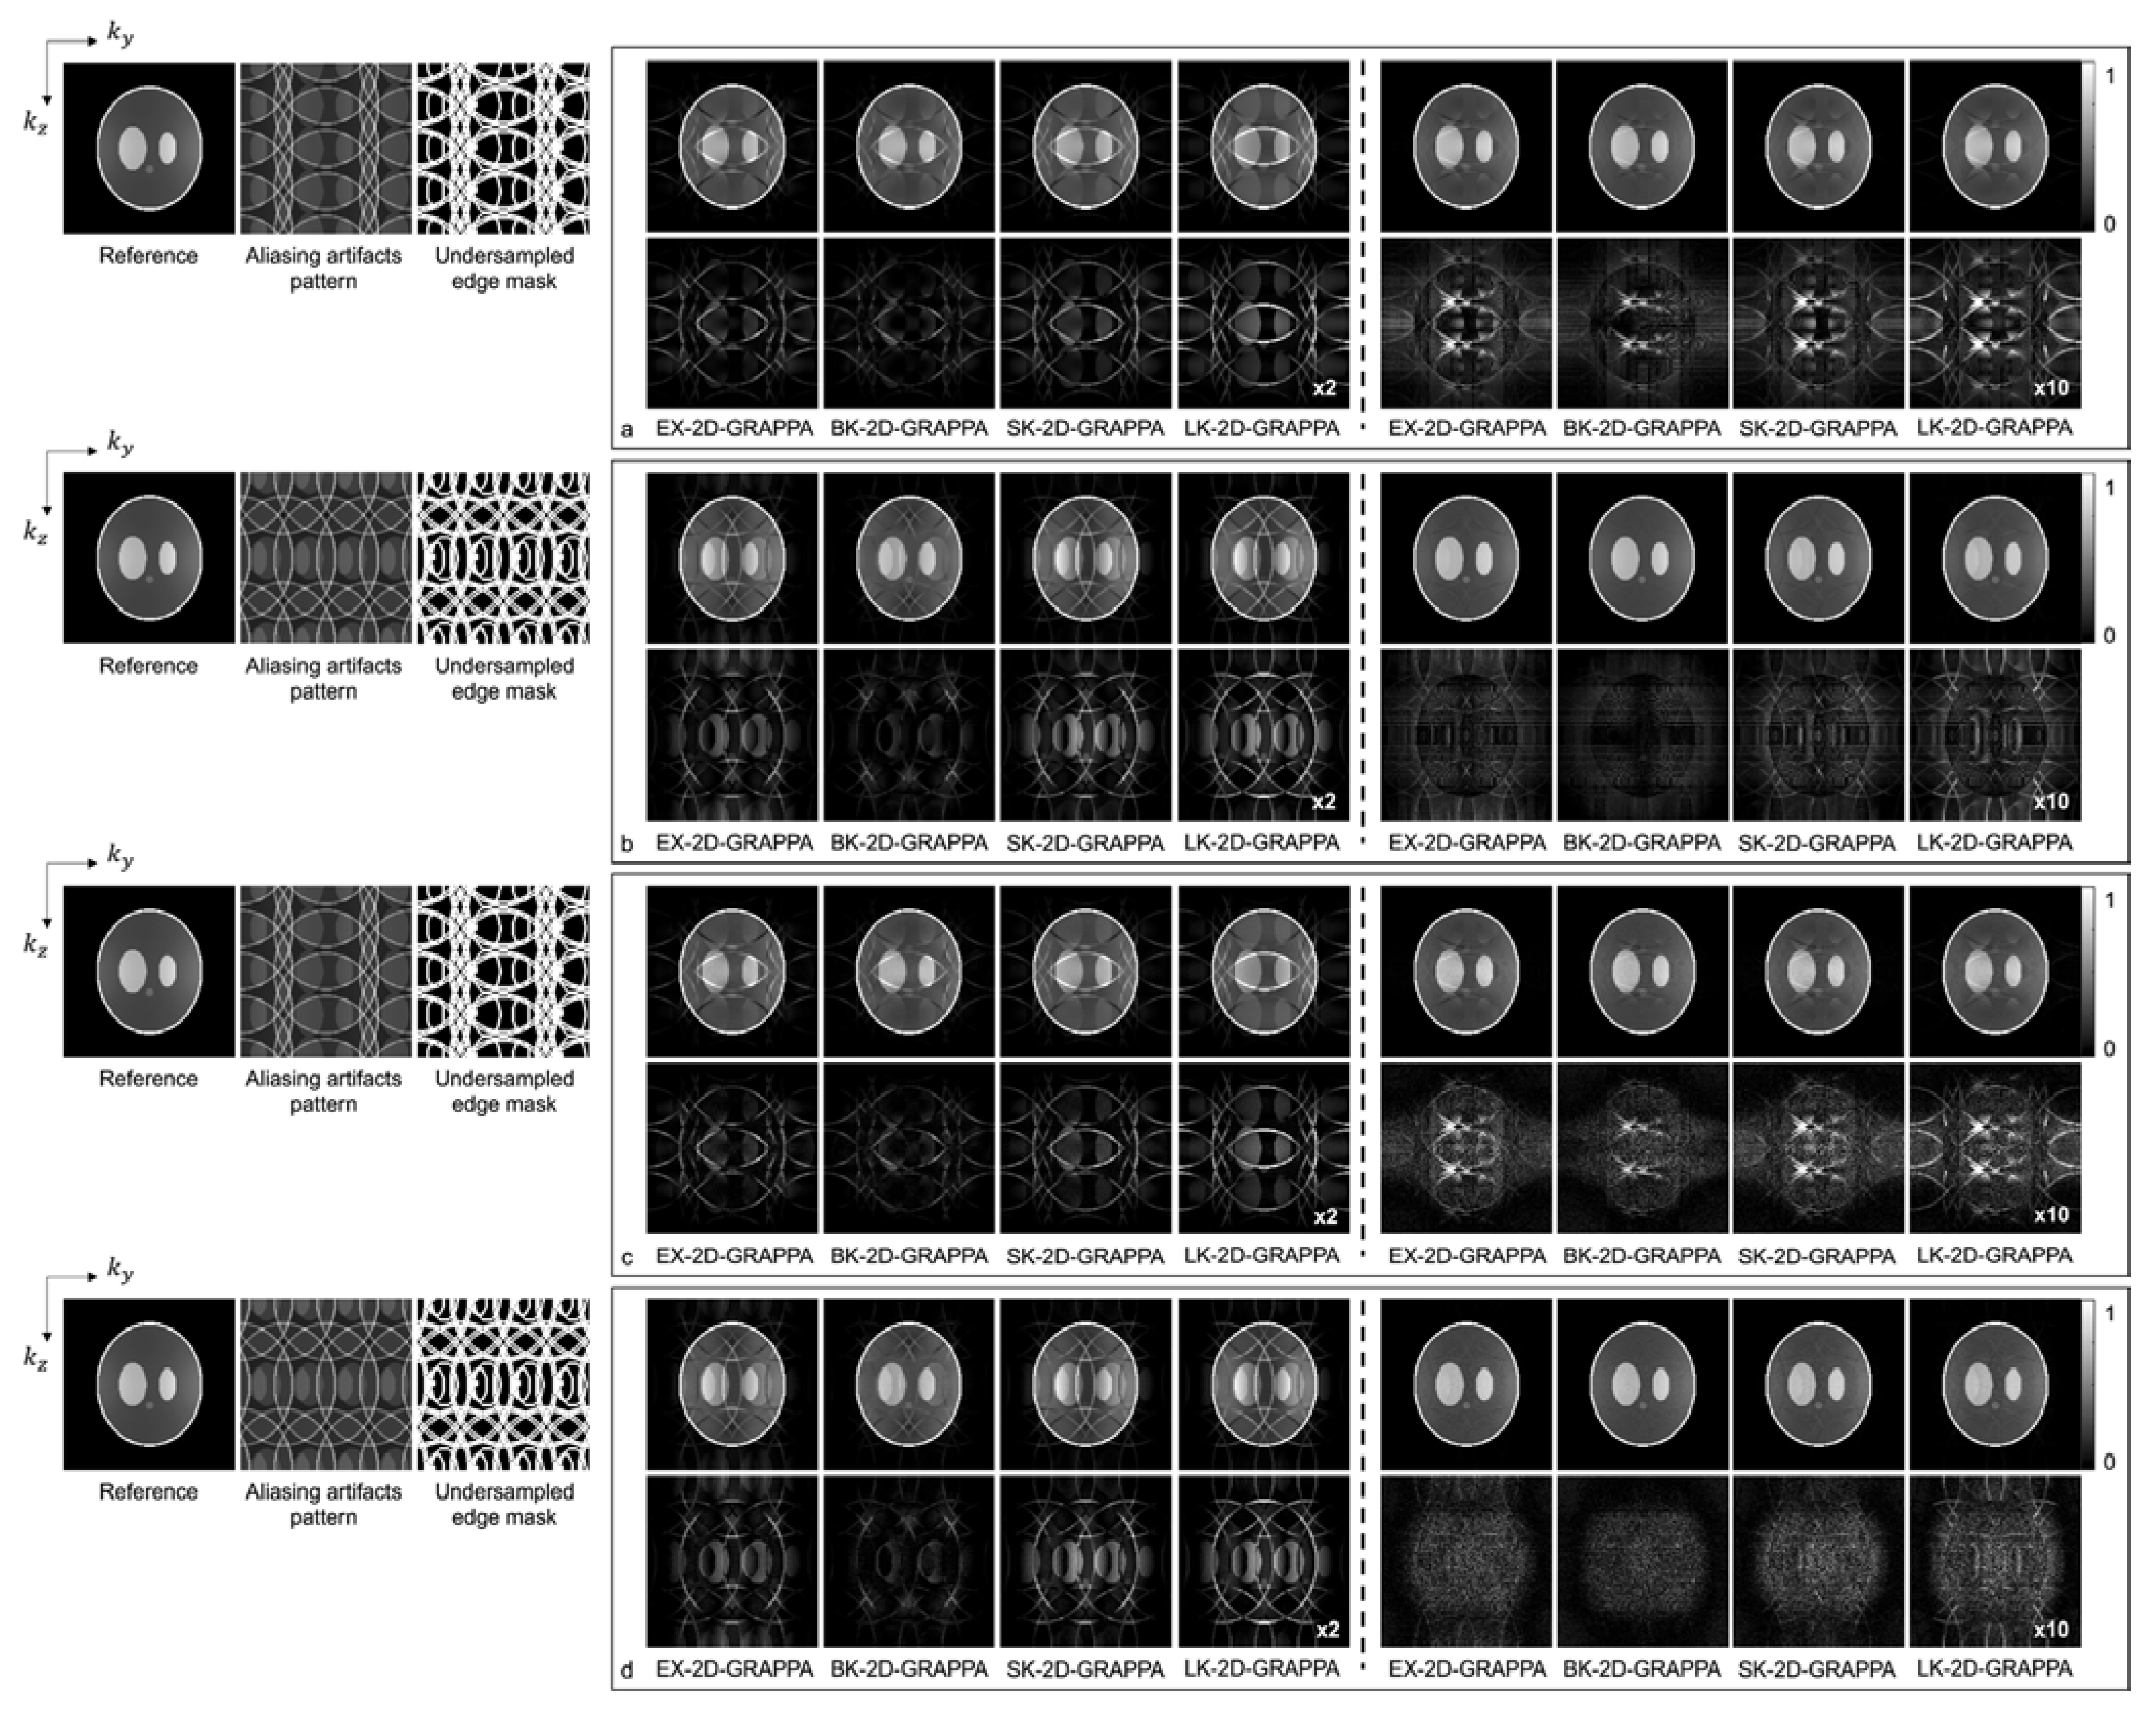

Figure 7 and Figure 8 present the reconstruction results of the 2D-GRAPPA algorithms when the total AF was increased to eight (Ry × Rz = 2 × 4 or 4 × 2) for computer simulation and the acquired data, respectively. Figure 7a–d shows the images reconstructed from noise-free and noise-added simulation data, respectively. Figure 7a,c was obtained when the kz direction was more accelerated (i.e., Ry × Rz = 2 × 4), and (b,d) were acquired when the ky direction was more accelerated (i.e., Ry × Rz = 4 × 2). On the left of each figure, a reference image with fully sampled k-space data, an image displaying the pattern of aliasing artifacts and an undersampled edge mask are also presented. In Figure 7a–d, the top rows display the reconstructed images using 32 × 32 k-space reference lines, and the bottom rows show the difference images between the complex-valued reference and the reconstructed images. The images from columns 1–4 and 5–8 were reconstructed with the basis and expanded kernels, respectively. The applied reconstruction algorithms are listed below the difference images.

Figure 7.

The reconstruction results of 2D-GRAPPA algorithms for simulation data with AF = 8. (a–d) were reconstructed from noise-free and noise-added data, respectively. Images in (a,c) were obtained when kz direction was more accelerated (2 × 4), and images in (b,d) were obtained when ky direction was more accelerated (4 × 2). Columns 1–4: basis kernel. Columns 5–8: expanded kernel.

Figure 8.

The reconstruction results of 2D-GRAPPA algorithms for (a,b) anthropomorphic head phantom and (c,d) in vivo data with AF = 8. The top rows in (a,c) were obtained when kz direction was more accelerated (2 × 4) and those in (b,d) were obtained when ky direction was more accelerated (4 × 2). Columns 1–4: basis kernel. Columns 5–8: expanded kernel.

Figure 8 shows the reconstructed images of the acquired (a,b) phantom and (c,d) human brain data, where asymmetric acceleration factors were used. For (a) and (c), the kz direction was more accelerated (i.e., Ry × Rz = 2 × 4), and for (b) and (d), the ky direction was more accelerated (i.e., Ry × Rz = 4 × 2). In addition to the reconstructed images, a reference image with fully sampled k-space data, an image displaying the pattern of aliasing artifacts and an undersampled edge mask are presented on the left. In Figure 8a–d, the top rows display the reconstructed images using 32 × 32 k-space reference lines, and the bottom rows show the difference images between the complex-valued reference and the reconstructed images. As with the computer simulation, images in columns 1–4 and 5–8 were reconstructed using the basis kernels and the expanded kernels, respectively.

As demonstrated by Figure 5, Figure 6, Figure 7 and Figure 8, the number of aliasing artifacts increased as the total AF increased from 4 to 8. In general, the images reconstructed by the BK-2D-GRAPPA algorithm showed the smallest difference from the reference image in the noise-free (Figure 7a,b) and the noise-added (SNR = 30 dB) simulation data (Figure 7c,d). In addition, the quality of the reconstructed image was improved when the expanded kernel size was utilized. As shown in Figure 8, the BK-2D-GRAPPA algorithm also showed the smallest number of aliasing artifacts in the phantom and in vivo data, regardless of which direction was more accelerated. The number of residual aliasing artifacts also decreased with the expanded kernel size.